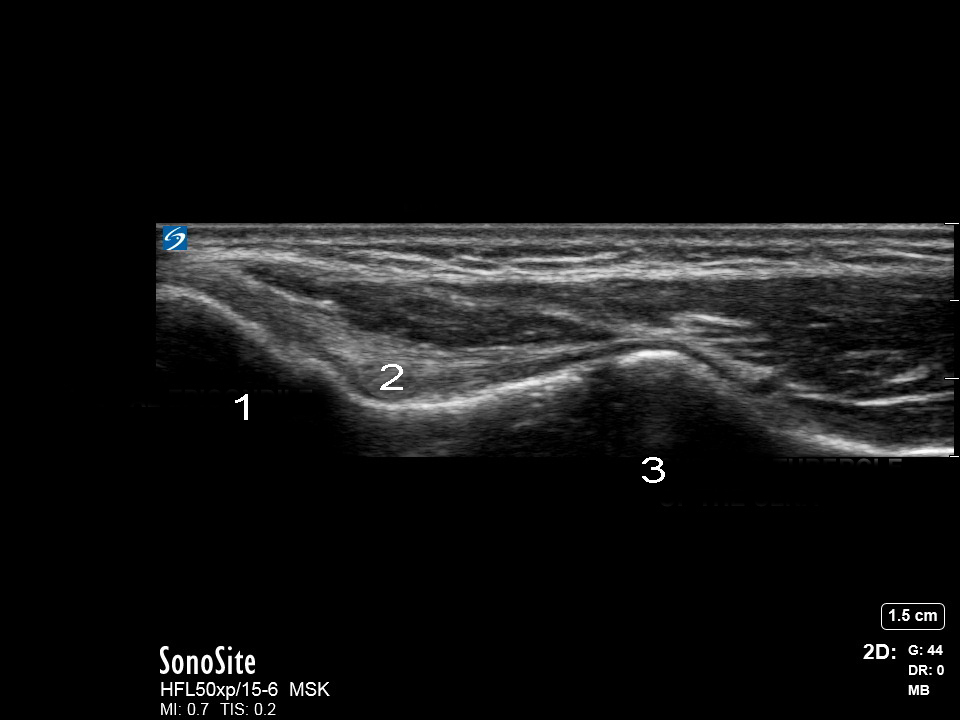

肘部尺侧副韧带图像

内上髁

尺侧副韧带 (UCL)

尺骨高耸结节